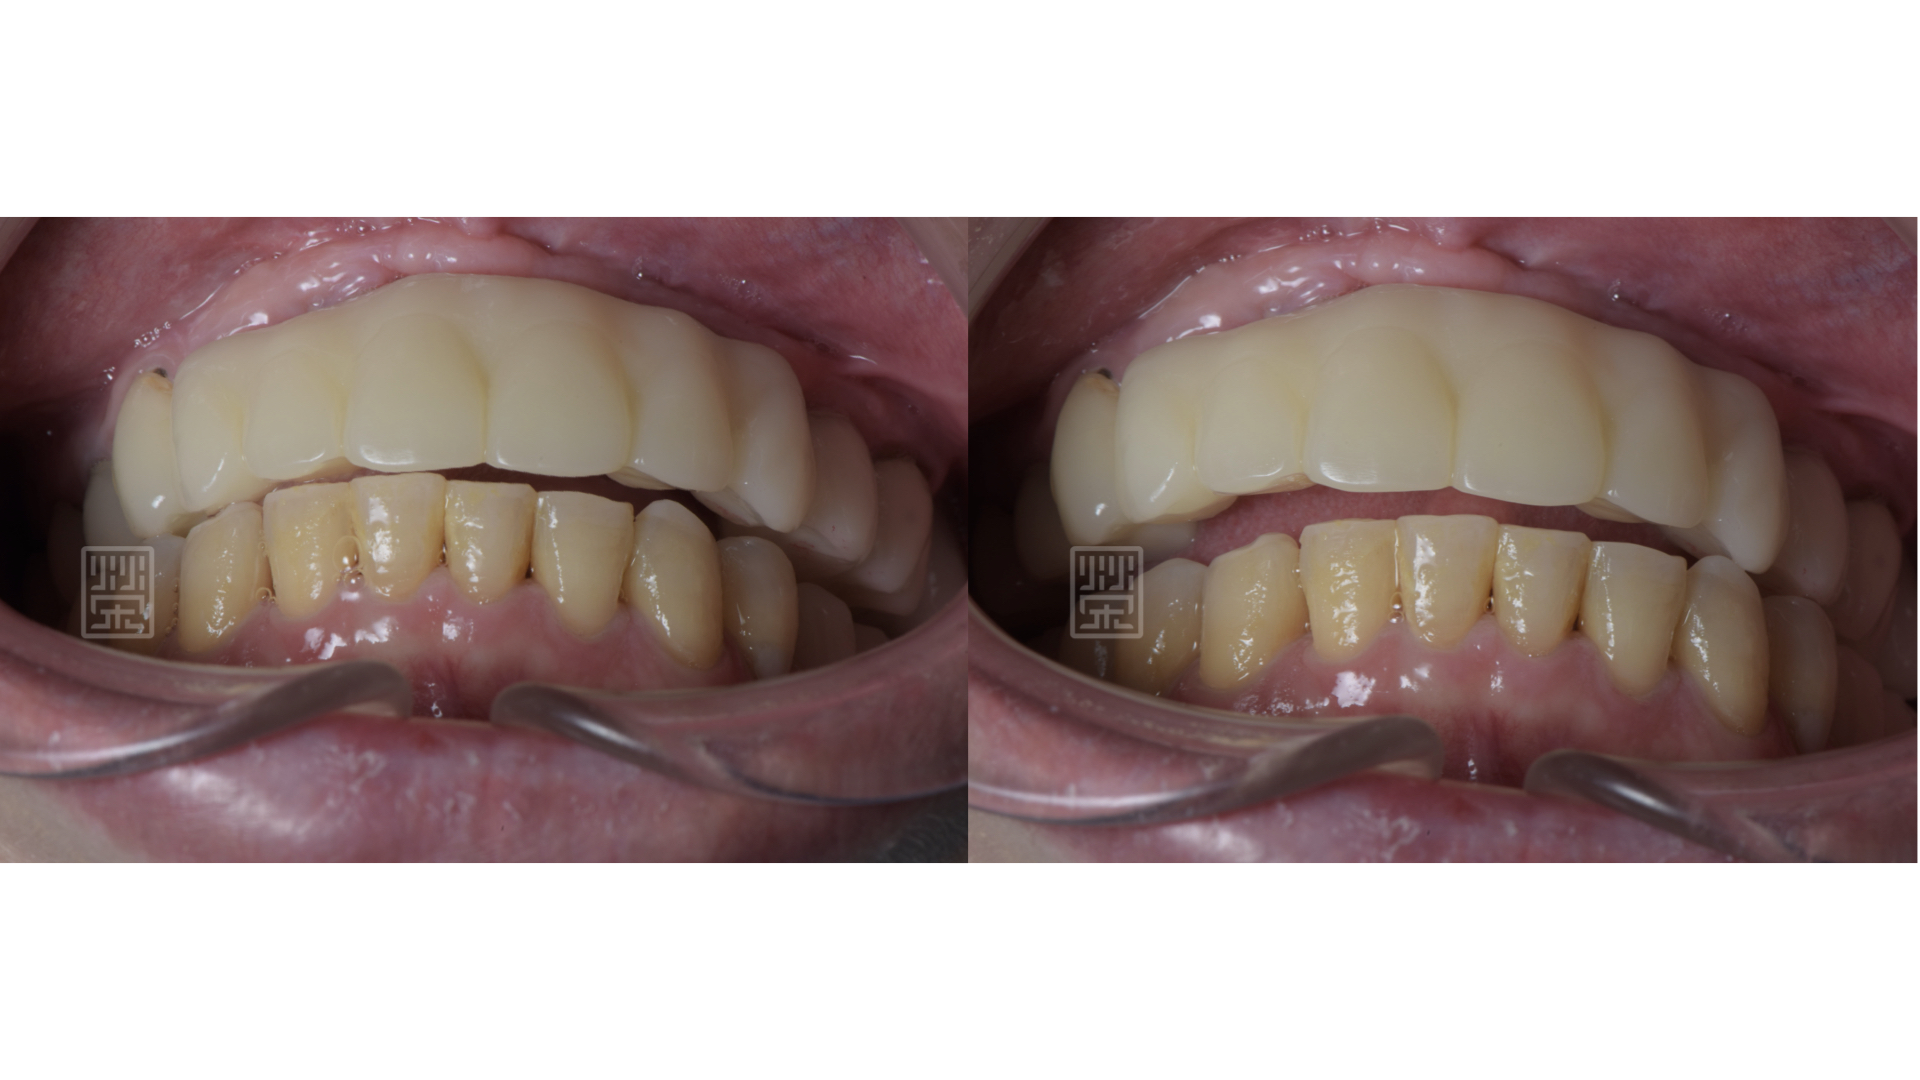

矯正後,再將門牙拉長,達到理想的牙齒的長度

適當分配牙齒導引位置,保護前後牙